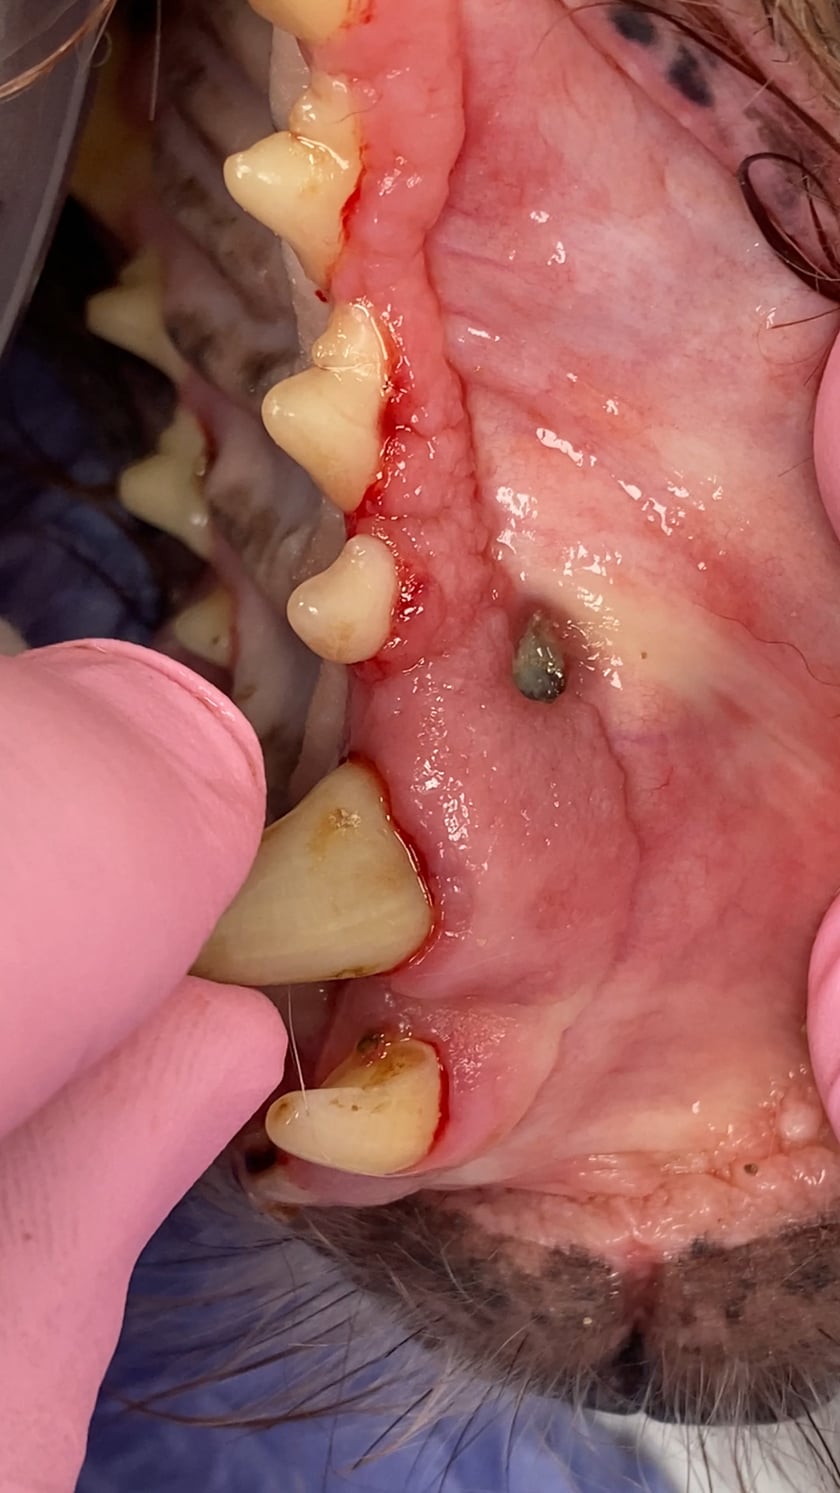

This upper canine tooth has an infection around the root that has burst out on the side of the gum (parulis) and the tooth is highly modile due to damage by the infection to the support tissues